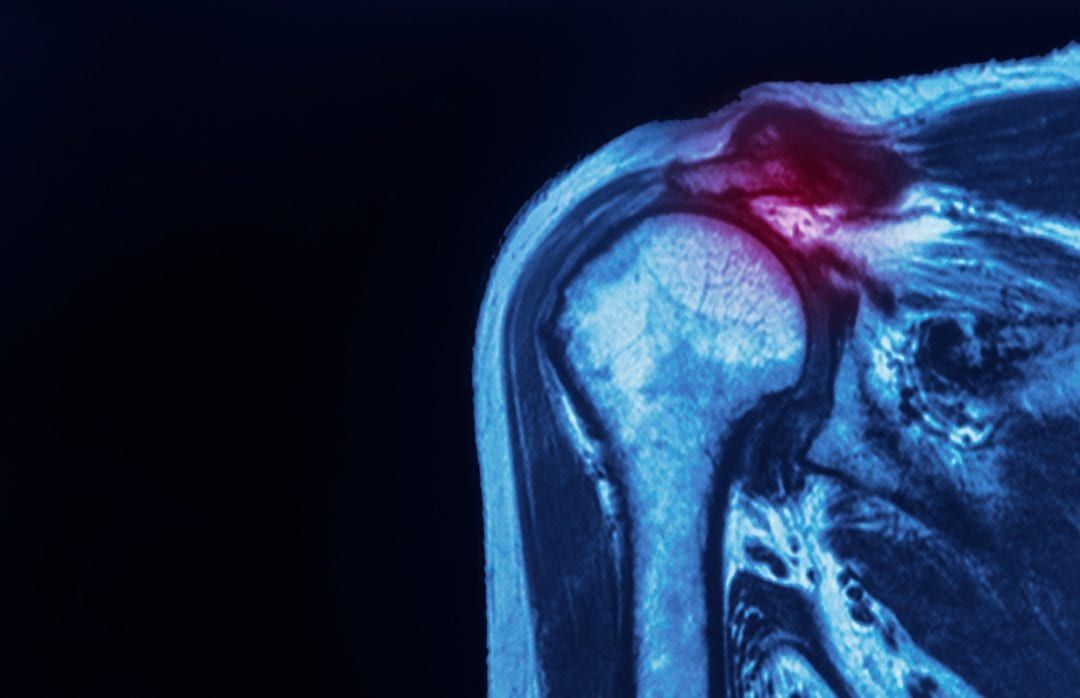

Rotator Cuff Injury What is it? Diagnosis & treatment for Rotator cuff injury

From hawkesphysiotherapy.co.uk

Rotator Cuff Injury What is it? Diagnosis & treatment for Rotator cuff injury Does Rotator Cuff Injury Affect The Elbow your rotator cuff allows you to lift your arms and reach upward. It details the symptoms of the three main causes of rotator cuff pain—a tear, tendinitis, or tendinosis. this article discusses rotator cuff pain. There are 2 main causes of rotator cuff tears: the most common cause of elbow and shoulder pain is tendinitis — an. Does Rotator Cuff Injury Affect The Elbow.